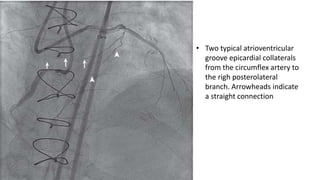

• Two typical atrioventricular

groove epicardial collaterals

from the circumflex artery to

the righ posterolateral

branch. Arrowheads indicate

a straight connection